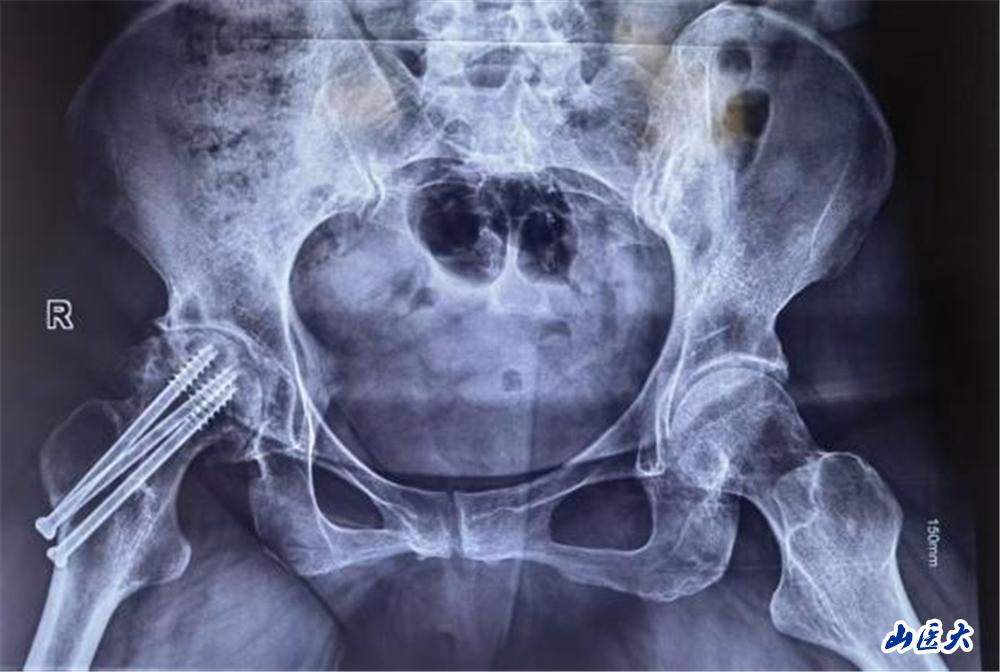

陈大姐饱受股骨头坏死折磨3年,近一个月疼痛加重,行走困难。面对患者强烈的保髋愿望,医疗团队术前通过影像学检查及血管评估,精准分析患者股骨头坏死范围及血供情况,为其量身定制了“带血管蒂的腓骨瓣移植”手术方案。这一术式能重建股骨头血运,延缓甚至避免关节置换,但对医生的显微外科技术要求极高。

手术当日面临巨大挑战,医疗团队需在患者腓骨处截取长约6cm的带血管骨瓣,并在显微镜下将细如发丝的旋髂外侧动脉与股骨头供血血管吻合。5个半小时的奋战,每一步都考验着团队的默契与技艺。

王建国凭借多年经验,精细剥离血管,避免损伤神经;团队其他手术医师在显微镜下,凝神屏息,以比头发丝还细的缝合线完成血管吻合,确保血流通畅。在大家的密切配合下,手术取得了圆满成功。